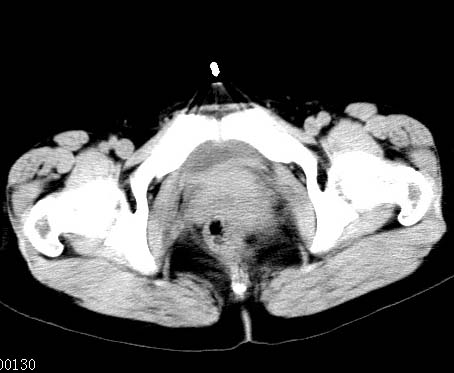

女性 病人 44岁 盆腔 下腹部痛1天!

盆腔内低密度为主混杂等密度及少许囊样与班状钙化影,如果做了肠道准备就好了。支持畸胎瘤。当然做mri会更好

典型的双侧附件畸胎瘤.

支持各位大侠观点.病人有急性腹痛,需除外有扭转可能.建议mri.

盆腔多发畸胎瘤,较为典型。